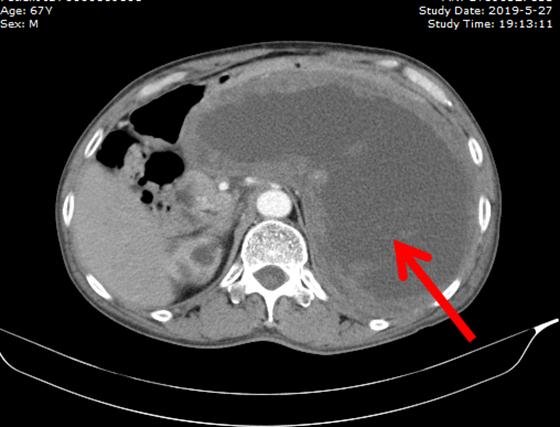

图右囊性肿块即唐大爷腹部巨大肿瘤

术中,两位专家也惊讶于唐大爷腹中的肿瘤:大小竟约25公分,与胃、脾脏关系紧密,颇难分离,肿瘤内部充满了褐色的液体。3个小时,术者都在小心翼翼地将肿瘤从结肠、胰腺、肾脏等脏器剥离,最终完整切除,并行全胃切除、食空肠袢式吻合,整个过程达5小时。手术结束,肖广发教授的手术服已浸满汗水。